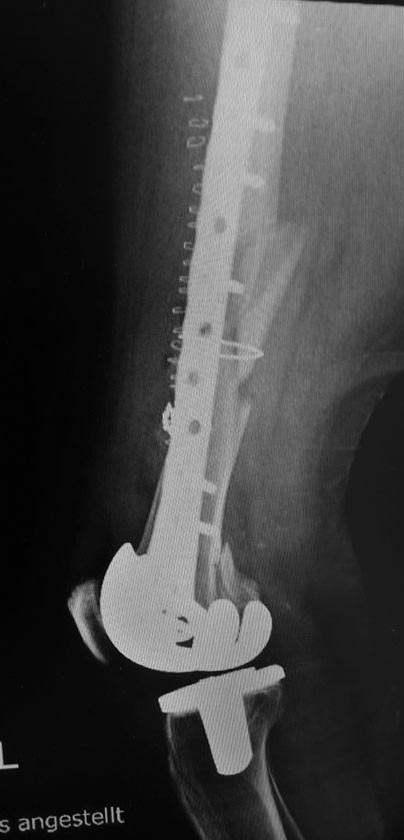

эКак оказалось в нашей ЦРБ сделали уже сегодня шеф решил без СТ. Пациент 41 года с большим количеством патологии. То есть полных 76 лет.

Норм остеосинтез но я в данном случае только за аппарат

Принципиальный момент- стабилен ли бедренный компонент? Если компонент изначально стабилен, что в данном случае мало вероятно), то все ок. Наилучшие результаты при использовании ИМ остеосинтеза (хотя могут быть проблемы с репозицией и размером гвоздя), затем блокированные пластины, затем все остальное ( последнее время много статей про применение аппаратов наружной фиксации). В данном случае длинна пластины корректная, но в зоне перелома слишком много металла, выше перелома должно быть 4-5 винтов, все бикортикально, с чередованием с пустыми отверстиями. То, что внизу торчат винты не очень good, но не так страшно. Консервативное лечение сопряжено с высоким риском летальности в течение первого года после травмы, вполне сравнимым с не оперированными шейками. Ключевой вопрос - стабильность бедренного компонента, теперь риторический).

А что правда кто-либо считает этот остеосинтез хорошим? По-моему беда! Шансов на сращение крайне мало, а для пожилого человека это может быть конец. Все принципы нарушены...

76 лет, остеопороз. В таких условиях требуется максимальное сохранение кровоснабжения в зоне перелома и фиксация с соблюдением принципа шинирования. Оно может быть накостным, интрамедуллярным или при помощи АНФ. В данном случае операция открытая, очень травматичная, куча винтов в зоне перелома, которые там неизвестно зачем, ну и серкляжи, которые могут стать последней каплей в убийстве кости. Из хорошего это действительно длина пластины, но при таком расположении винтов она (длина) не работает

Скорее всего, бедренный компонент не отклеился, так что это Rorabeck-Lewis II. Традиционный вариант - пластина с угловой стабильностью закрыто. Или две, чтобы от варусного коллапса подстраховаться. Мне больше бы импонировал антеградный закрытый интрамедуллярный остеосинтез.

Количество эндопротезирований растёт, поэтому с подобными случаями придётся сталкиваться чуть не каждому из нас. Или каждому. Думаю, следование принципам - абсолютная стабильность вокруг компонентов протеза и относительная - вне, не может вызывать особых дискуссий.

К сожалению (при этом желаю и хирургу, и пациенту удачи), выполненное вмешательство оставляет крайне мало шансов больному. Именно потому, что для метадиафизарной части перелома доктор пытался добиться абсолютной стабильности. Что не приемлемо при остеопорозе. Там и случится проблема, возможно, в самое ближайшее время. Я бы использовал остеосинтез пластиной - миниинвазивный для метадиафизарной зоны (как я понимаю, мы предполагаем, что ножка стабильна? ОК). Вот эти винты и завитушки на диафизе лишние и только демонстрируют не вполне гуманное отношение к биологии в этой зоне.

Учитывая, что протез без стабилизатора, межмыщелковое пространство абсолютно свободно и оптимальным вариантом в данном случае мог стать ретроградный интрамедуллярный остеосинтез с блокированием как самый малоинвазивный и сохраняющий и без того того повреждённое кровоснабжение через надкостницу. Выполненный накостный остеосинтез нельзя отнести к стабильному, к тому же по представленным рентгенограммам складывается впечатление, что винты проведённые через мыщелки обычные кортикальные, не фиксированы в пластине, серкляжные швы не придают стабильности. Потребуется длительная контролируемая реабилитация. Не исключается по результатам рентгенконтроля повторное оперативное вмешательство (костная пластика или всё-таки переход на интрамедулляный остеосинтез)